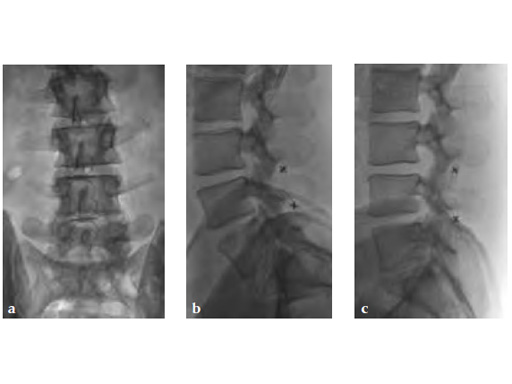

Case provided by Paul W Pavlov, Nijmegen, The Netherlands

32-year-old male with neurogenic claudication due to spinal stenosis (degenerative bulging discs). Complete relief of symptoms.